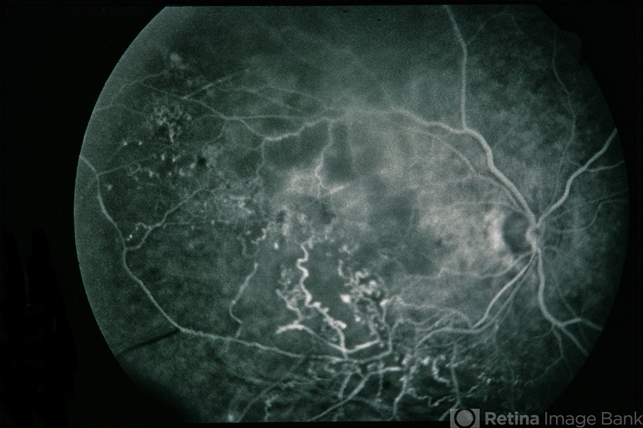

BRVO - Massive Exudate from Collaterals

BRVO Massive Exudate from Collaterals

branch retinal vein occlusion (BRVO), exudate, collaterals

66-year-old female with BRVO - massive exudate from collaterals, 20/70 OD; 20/25 OS in 1985; +HTN, glaucoma; 20/200 OD 1987.